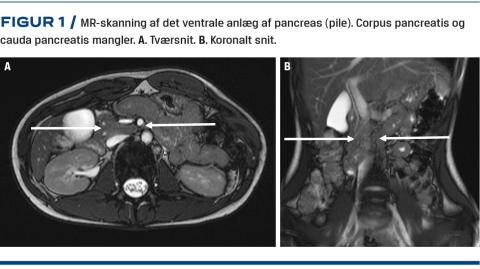

En 18-årig kvinde, som havde fået diagnosticeret Aspergers syndrom, fik over en måned mavesmerter, kvalme, opkastninger, nedsat fødeindtag og vægttab. Hun blev via egen læge henvist til ultralydskanning af abdomen. Ved skanningen blev der påvist bilaterale nyrecyster og rejst mistanke om atrofi af pancreas, da caput pancreatis – men hverken corpus pancreatis eller cauda pancreatis (Figur 1) – kunne ses. Der blev foretaget en gastroskopi og taget biopsier fra duodenum, hvor der blev fundet upåfaldende forhold. Ved en MR-skanning af pancreas påvistes agenesi af det dorsale pancreasanlæg. Størstedelen af symptomerne aftog spontant. På mistanke om pancreassygdom blev patienten henvist til videre ambulant udredning på et universitetshospital. Fraset Aspergers syndrom var patienten tidligere sund og rask. Hun klagede fortsat over mavesmerter, som var lokaliseret under venstre ribbenskurvatur og forværredes postprandialt. Vægttabet var aftaget, og hun havde taget på igen. Der forelå blodprøver, som viste, at hun havde et lavt D-vitamin-niveau (20 nmol/l) og et normalt niveau af glykeret hæmoglobin (41 mmol/mol). En supplerende udredning viste normal faeceselastase (210 µg/g), hvorfor man ikke havde mistanke om pancreasinsufficiens. Derimod blev der påvist hypomagnesiæmi med et magnesiumniveau på 0,64 mmol/l. Pga. hypomagnesiæmien blev patienten undersøgt genetisk for Gitelmans og Bartters syndrom. Disse undersøgelser viste normale forhold. En døgnurinopsamling viste, at der var et renalt betinget magnesiumtab. Der blev foretaget behandling med infusion af magnesium, uden at P-magnesiumniveauet steg nævneværdigt. Der blev påbegyndt behandling med spironolacton mhp. at forebygge dette renale tab.

DPA skyldes manglende dannelse af den dorsale pancreasknop fra duodenums endodermale beklædning. Dermed dannes kun caput pancreatis. Fra 1911 til 2015 er der beskrevet 106 cases i litteraturen. Tilstanden diagnosticeres stadigt hyppigere, og halvdelen af tilfældene er beskrevet i perioden 2008-2015. Formentlig diagnosticeres tilstanden nu hyppigere pga. forbedringer af og lettere tilgængelighed af billeddiagnostik. Klinisk har patienter med DPA mavesmerter, diabetes, pankreatitis og eksokrin dysfunktion af pancreas. Der kan også være tale om et tilfældigt fund ved billeddiagnostik. Hos patienter med DPA er der fundet øget risiko for udvikling af neoplasi og malignitet i pancreas. I et systematisk review om DPA fik ni ud af 53 patienter, som havde DPA og blev diagnosticeret i perioden 2008-2015, foretaget total pankreatektomi pga. adenokarcinom i pancreas [5].